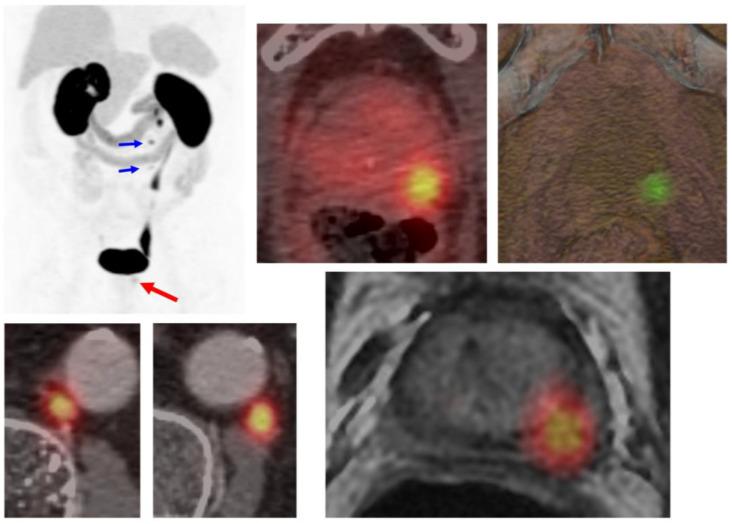

Prostate-specific membrane antigen positron emission tomography/computed tomography (PSMA-PET/CT) has emerged as a game-changing imaging modality in prostate cancer, offering superior sensitivity and specificity compared to conventional imaging techniques. Its increasing adoption has significantly influenced radiotherapy decision-making, yet its true clinical impact remains under investigation. This narrative review explores the role of PSMA-PET/CT in guiding radiotherapy decisions across different clinical scenarios, from primary treatment planning to biochemical recurrence and oligometastatic disease. We assess its impact on target delineation, treatment modifications, and overall patient management while addressing existing knowledge gaps.

前列腺特异性膜抗原正电子发射断层扫描/计算机断层扫描(PSMA-PET/CT)已成为前列腺癌领域一项具有变革性的成像模态,与传统成像技术相比,具有更高的敏感性和特异性。其应用的日益广泛显著影响了放疗决策,但它的真正临床影响仍在研究中。这篇叙述性综述探讨了PSMA-PET/CT在不同临床场景中指导放疗决策的作用,从初始治疗计划到生化复发和寡转移疾病。我们在解决现有知识空白的同时,评估其对靶区勾画、治疗调整和整体患者管理的影响。